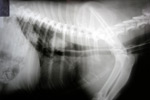

Bone

Bone heals in the same way as any wound and differs only in the maturation phase following the deposition of the granulation tissue bed.

The type of healing which subsequently occurs will depend principally on the degree of stability and immobilisation of the fracture site. An adequately stabilized wound (often achieved with the use of bone plates, external fixateurs or pins will result in the conversion of mesenchymal cells into osteoblasts and bone deposition.

Inadequate stabilization will result in the transformation of mesenchymal cells into chondroblasts and the deposition of fibrocartilage into the fracture site. This will result in a “non-union”. In response to this, the bone ends deposit additional periosteal new bone and a so-called hypertrophic non-union develops.